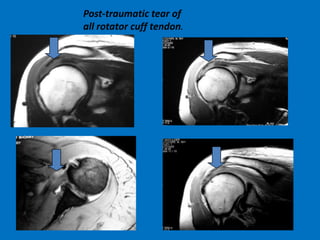

Post-traumatic tear of

all rotator cuff tendon.